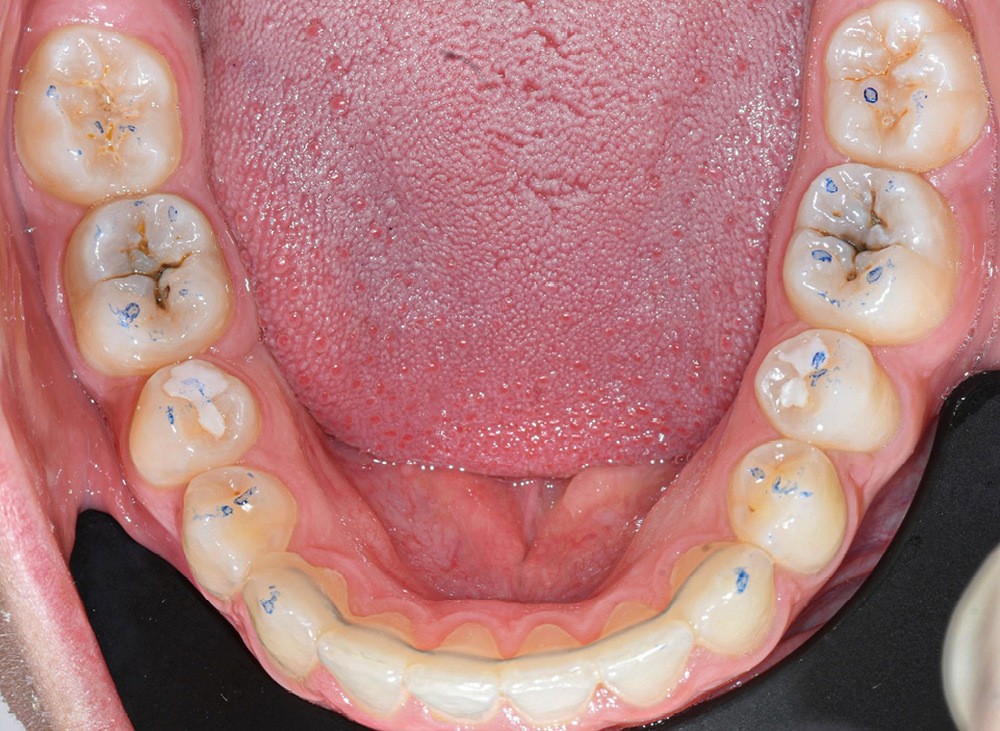

Nous détaillons la technique à travers le cas d’une jeune fille de 18 ans présentant des lésions carieuses sur quatre dents (fig. 1 à 14).